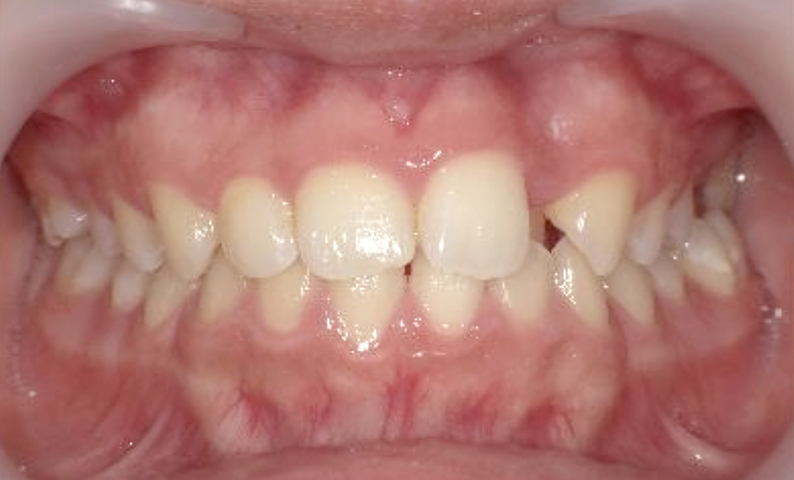

症例_001 上下顎の部分矯正

治療期間:12ヶ月金額:54万円+税女性前歯のガタガタ逆八の字

| Before | After |